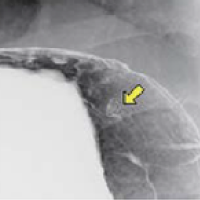

기초검사와 일반검사에서 얻은 자료를 토대로 각종 영상판독 소견을 종합하여 종합검진결과를 완성합니다. 검진결과를 참고하여 필요한 경우에는 개인맞춤 처방을 제공합니다. 또한 내과외래 진료도 진행하여 환자들의 내과진료를 담당합니다. 소화기 내과에서는 위/대장 내시경 검사 및 판독결과 상담을 통해 소화기질환 및 암검진에 대한 상담 및 처방을 진행합니다.